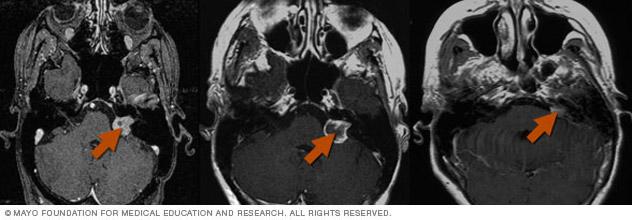

Gamma Knife radiosurgery results

Gamma Knife radiosurgery uses multiple tiny beams of radiation to shrink tumors. The left brain scan shows a pretreatment image of a noncancerous tumor — an image enhanced by the use of a special dye, called a contrast agent. At six months after treatment (middle image), the tumor appears slightly larger but doesn't take up as much of the contrast agent — isn't as bright in the center. This indicates a positive treatment effect. At seven years (right scan), the tumor appears much smaller.